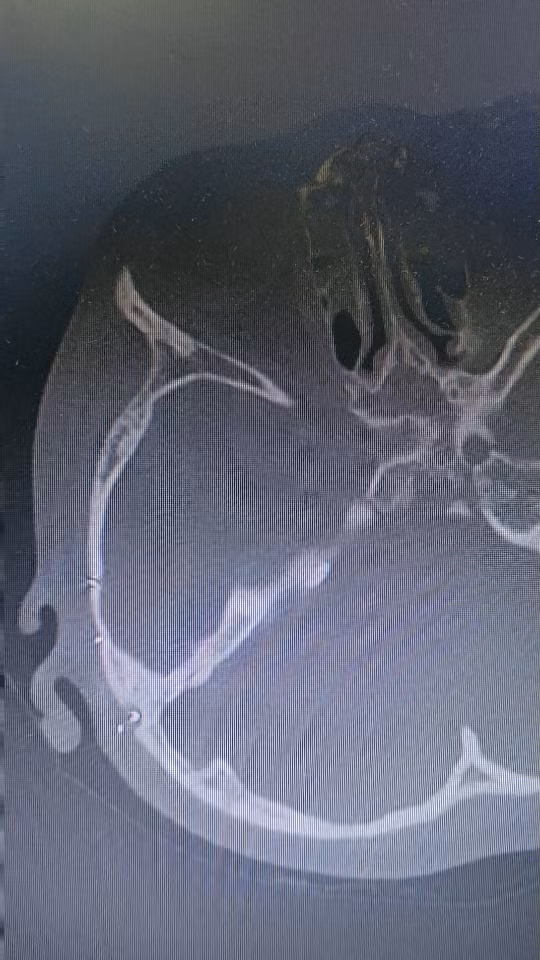

为检查耳科,2024-12-26乳突CT ,未行MR检查

时间跨度1年半,发现乳突骨质有破坏,怀疑胆脂瘤复发。